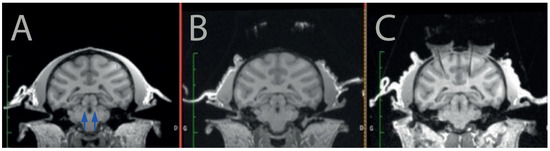

Figure 1. Targeting the LC with MRI. The monkey was first scanned before surgery (A) to identify potential trajectories toward the LC (arrows) and to reach it from the surface of the skull without piercing a ventricle or a blood vessel. After the recording cylinders and headpost were implanted surgically, we marked a stereotaxic grid with iodin and scanned the monkey with the grid in place (B). After the grid hole that would enable to reach the LC was identified on this second scanner, we scanned the monkey a third time with an electrode inserted in the corresponding grid hole (C). The artefact generated by the electrode is clearly visible on the image, and it shows that the trajectory is adequate to target the LC.

2.3.1. Head Post and Recording Cylinders

First, we scanned the monkey using a 3T MRI scanner (Siemens, Erlangen, Germany) to determine the position of the LC and calculate a safe trajectory for the injection devices (Figure 1A). Note that even if the LC was not visible on our MRI scans, we could easily identify its position on each animal using standard landmarks and brain atlases. Once the position of the LC was identified in each hemisphere, we determined the position of the recording cylinder on the skull such that the angle and the position allowed us to reach the LC without puncturing lateral ventricles or major blood vessels such as the posterior cerebral artery.

Then, we implanted the 2 recording cylinders (one on each hemisphere) as well as a head post on the skull of the animal by performing a sterile surgery under general anesthesia in a fully equipped surgical room. As classically performed for neurophysiology in monkeys, the recording cylinders were positioned on the skull at the intended stereotaxic coordinates (based on the MRI scans), and they were held in place using dental cement secured on the skull via platinum screws. The head-post (to hold the animal’s head), was also held in place via dental cement. Upon recovery from surgery, the monkey was progressively habituated to be head-fixed, such that it could tolerate recording sessions of about 1 to 2 h. After about 4 weeks of recovery after implantation, we opened the skull in each of the recording cylinders to allow access to the brain. We scanned the monkey again with a marked (iodin) stereotaxic grid (Crist Instrument) to identify which position should be used for accessing the LC in that grid (Figure 1B). Note that this could be performed before or after opening the skull. Subsequently, we verified the position of the LC in the coordinate of the stereotaxic grid using MRI and/or neurophysiology. To identify the injection site within the stereotaxic reference of the grid, we placed a tungsten recording electrode at a given depth in one of the grid holes, and the animal is scanned with the electrode in place. The artefact of the electrode is easily visible on T1 images (Figure 1C).